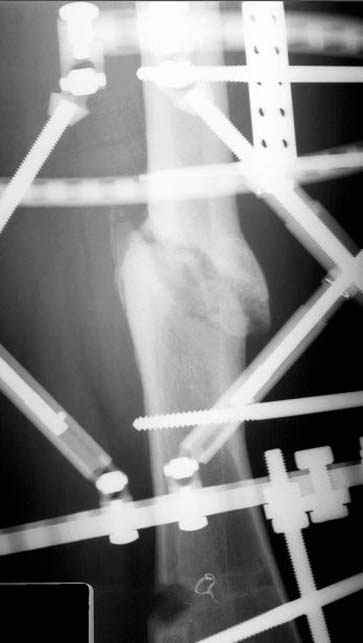

Несколько снимков из моей коллекции, чтобы разьяснить, почему мы до сих пор делаем различные варианты остеотомии.

На рисунке N1 предоперационный план лечения ложного сустава шейки бедра- линия ложного сустава, угол и направление введения импланта, клиновидная остеотомия в градусах и миллиметрах, второй снимок после коррекции, расчет, на сколько удлиняется конечность и размеры импланта;

N3 рисунок окончательный снимок, после операции моя рентгенограмма должен выглядеть примерно как эта картина. На N4 снимке клин перед удалением; N5 послеоперации 3 нед.; N6 окончательная рентгенограмма.

(доложен в Ст. Петербурге 2003 и в Москве 2004)

варус при проксимальном отделе 95 градусной пластиной.

пластическая модель; и коррекция бедра аппаратом Илизарова.

Имею другие снимки тоже, получится как отчет о моей работе.